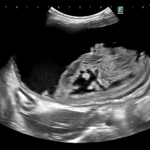

画像診断:特徴的な所見は述べらていませんが、CTで子宮の捻転基部が観察されました。

本症例は子宮水腫に続発した捻転と考えられました。ちいさな体で頑張ってくれました。